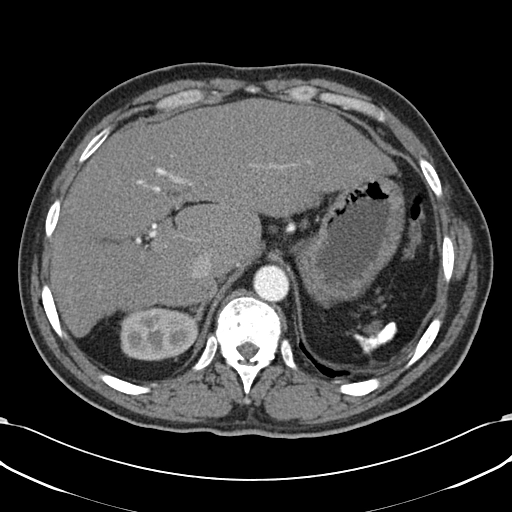

• Lách to (Splenomegaly)